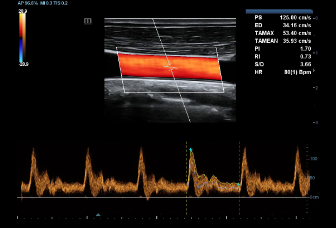

–ě—Ā–Ĺ–ĺ–≤—č–≤–į—Ź—Ā—Ć –Ĺ–į –≥–Ľ—É–Ī–ĺ–ļ–ĺ–ľ –Ņ–ĺ–Ĺ–ł–ľ–į–Ĺ–ł–ł –Ņ–ĺ—ā—Ä–Ķ–Ī–Ĺ–ĺ—Ā—ā–Ķ–Ļ –ļ–Ľ–ł–Ķ–Ĺ—ā–ĺ–≤, –ļ–ĺ–ľ–Ņ–į–Ĺ–ł—Ź Mindray —Ä–į–∑—Ä–į–Ī–ĺ—ā–į–Ľ–į —Ā–ł—Ā—ā–Ķ–ľ—É DC-60 Exp —Ā X-Insight, —á—ā–ĺ–Ī—č –ĺ–Ī–Ķ—Ā–Ņ–Ķ—á–ł—ā—Ć –≤—č—Ā–ĺ–ļ—É—é –Ņ—Ä–ĺ–ł–∑–≤–ĺ–ī–ł—ā–Ķ–Ľ—Ć–Ĺ–ĺ—Ā—ā—Ć –ł —ā–ĺ—á–Ĺ–ĺ—Ā—ā—Ć –≤–ł–∑—É–į–Ľ–ł–∑–į—Ü–ł–ł –≤–ļ—É–Ņ–Ķ —Ā –Ĺ–į–≥–Ľ—Ź–ī–Ĺ–ĺ—Ā—ā—Ć—é, –ł—Ā–ļ–Ľ—é—á–ł—ā–Ķ–Ľ—Ć–Ĺ–ĺ–Ļ –ł–Ĺ—ā–Ķ–Ľ–Ľ–Ķ–ļ—ā—É–į–Ľ—Ć–Ĺ–ĺ—Ā—ā—Ć—é –ł –ĺ–≥—Ä–ĺ–ľ–Ĺ—č–ľ –ĺ–Ņ—č—ā–ĺ–ľ.